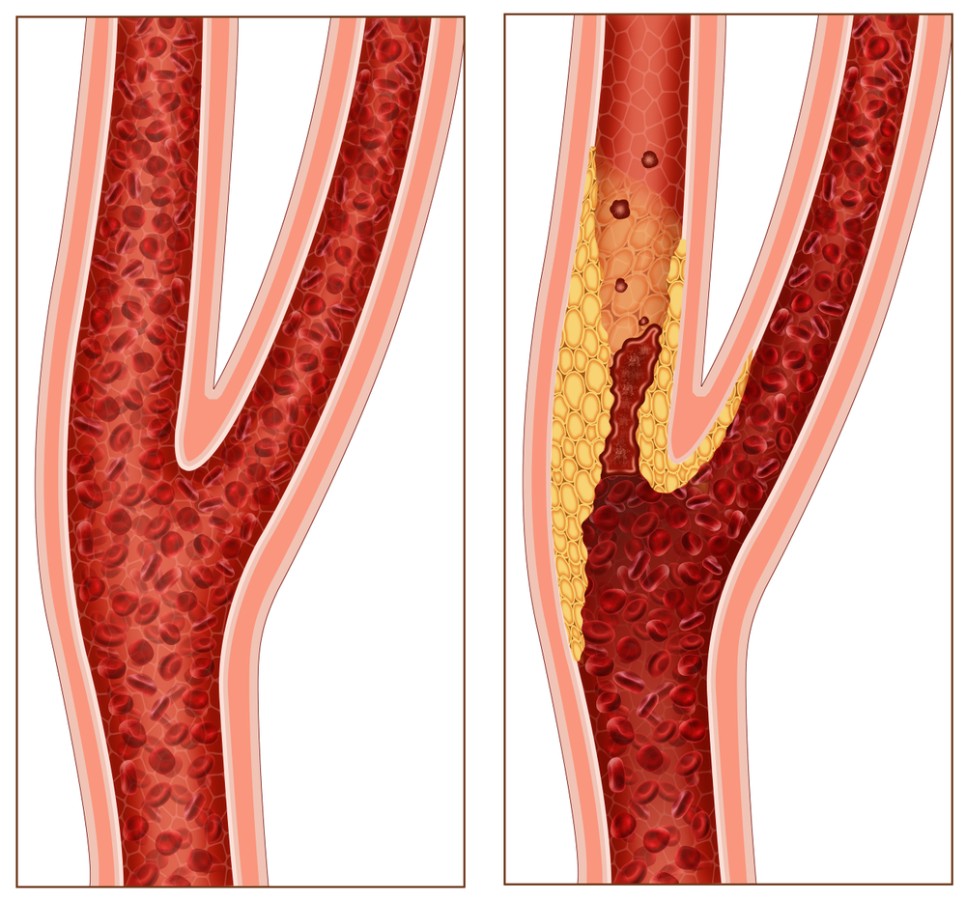

뇌로 가는 혈액의 80%를 보내는 목에 있는 중요한 혈관으로 경동맥경화가 진행되면 뇌졸중 발생 위험이 높아지기 때문입니다. 경동맥에 생긴 찌꺼기가 뇌혈관으로 흘러 들어가 뇌혈관을 막을 확률이 높아집니다.

경동맥협착증은 혈관벽의 병변으로 경동맥이 좁아지는 동맥경화증, 동맥벽이 찢어지고 박리되는 경동맥박리증, 큰 동맥 여러 곳에 일어나는 만성혈관염증은 고곡수동맥염 등이 있습니다.

경동맥 협착증의 증상으로는 특별히 초기 증상이 없는 것이 가장 무서운 점입니다. 혈관이 50~60% 절반 가까이 막혀도 특별한 경동맥협착증 증상이 나타나지 않아 치료 시기를 놓치는 경우가 많습니다.

하지만 경동맥이 60% 이상 막혀 어지럼증, 감각이상, 안면신경마비, 언어장애, 반신부전마비가 나타나는데 그때서야 아는 게 많습니다.